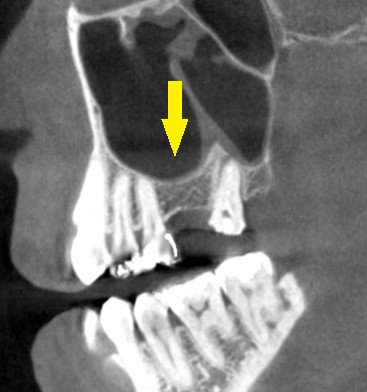

CTを撮影してみると、方向によっては、骨がありそうに見えますが、やはり十分な骨量とはいえませんでした。

ある程度の骨はありますので、ワイドインプラントを用いて、人工骨は使用せず、骨造成も行わないで、インプランント埋入が可能であると説明させていただきました。

ご納得いただけましたので、本日、ワイドショートインプラント、直径5.0mm、長さ7mmのインプラントを埋入しました。

下の写真、2段目が手術前のCT、3段目が手術後のCTです。